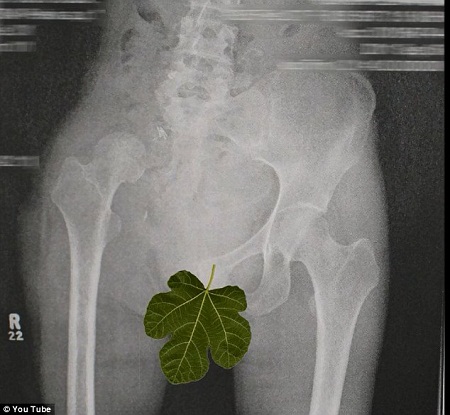

奧謝的手術(shù)X光片